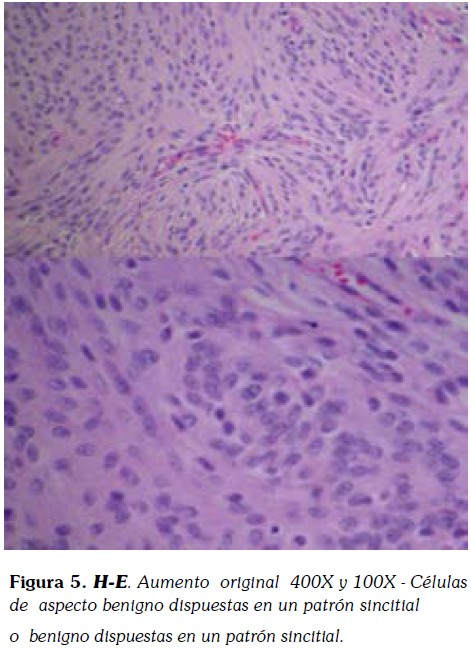

Histológicamente, el tumor fue reportado como formación por células dispuestas en racimos lobulados con zonas de espirales. Presencia de núcleos ovalados con cromatina fina granular y Actividad mitótica baja. Por inmunohistoquímica, las células mostraron una fuerte positividad para el antígeno de membrana epitelial. El diagnóstico final fue meningioma meningotelial.

Macroscópicamente, se evidencia una muestra fragmentada de 4x3x1cm constituida por porciones de un tejido homogéneo, blanquecino y grisáceo de aspecto fasciculado y consistencia intermedia. Histológicamente, los hallazgos correspondían a un meningioma convencional de patrón predominantemente meningotelial (4, 9,10).

El tumor presentaba una microarquitectura lobular constituida por células eosinofílicas de configuración sincitial, con bordes mal delimitados, y núcleos redondeados u ovales con nucléolos poco prominentes (Figura 4 , 5).